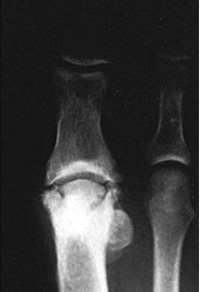

The term "Avascular Necrosis" refers to a condition where a portion of a bone dies due to diminished localized blood flow.  This results in degeneration of the bone, which is particularly problematic near a joint, as it may cause arthritis.  (See photo to the right.)

Avascular Necrosis of the first metatarsal bone at the big toe joint.  Note the whitened appearance (sclerosis) of the bone and the irregular joint surface suggesting arthritic changes in the joint.